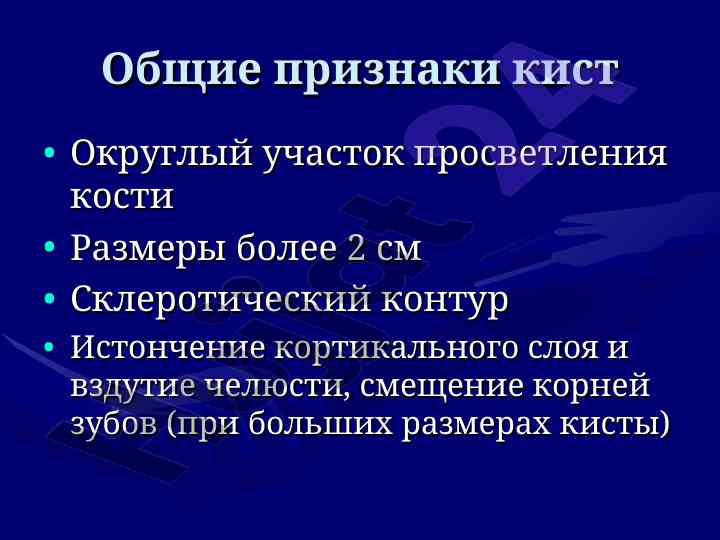

Данная лекция охватывает диагностические критерии, локализацию и структуру кист и опухолей челюстно-лицевой области, включая одонтогенные и неодонтогенные кисты.